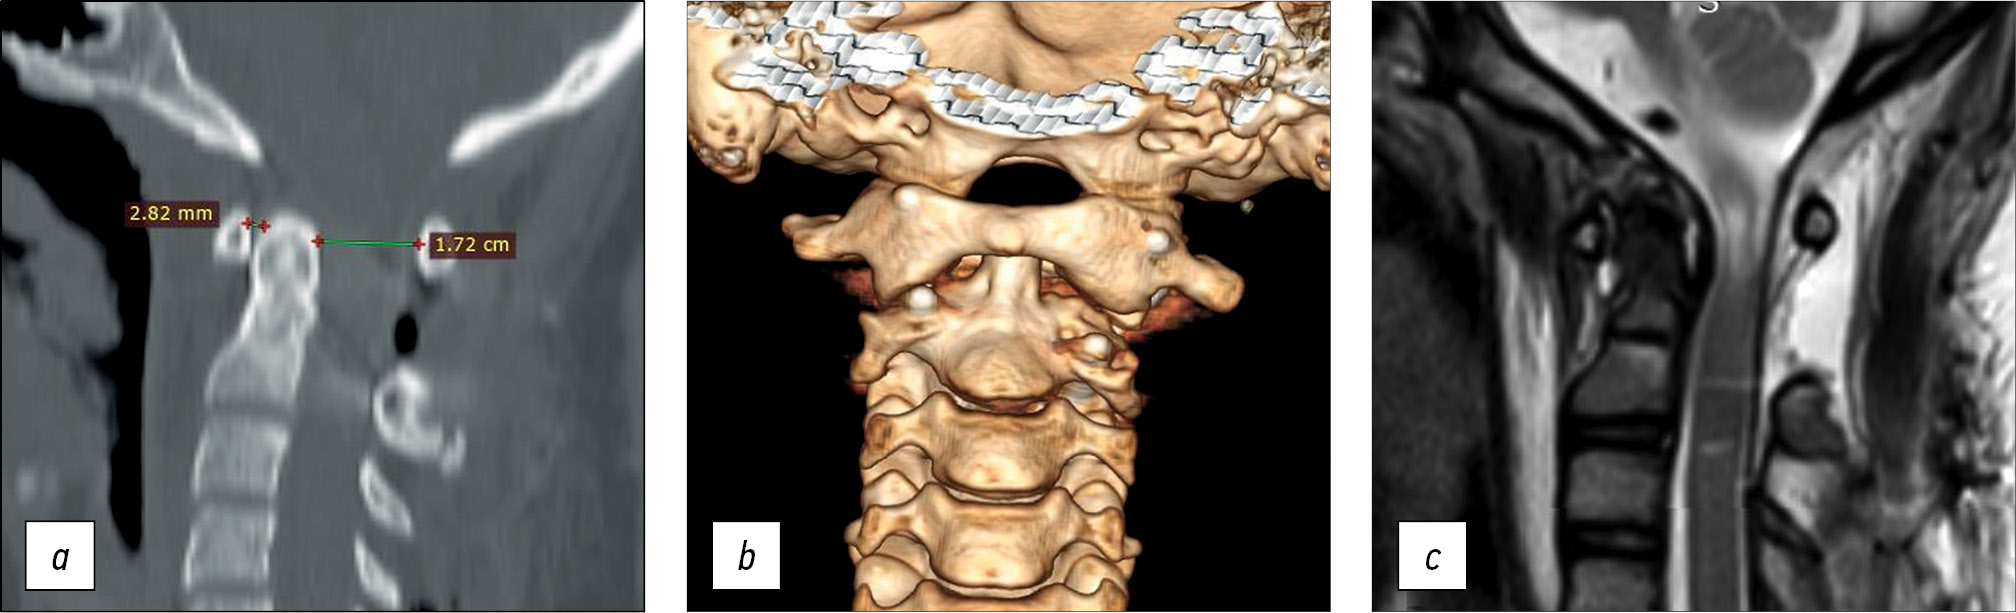

A 14-year-old female teen was admitted for a cervical spine screening examination in individuals with Down syndrome. She complained of progressive weakness in the upper and lower extremities and forced head position with rotation to the right for the past 3 months. Results of the CT and MRI of the cervical spine led to the following diagnosis: Down syndrome, rotational atlantoaxial blockage, left-sided chronic transligamentous subluxation of the C1 vertebra with spinal canal stenosis (Fielding–Hawkins type II), cervical myelopathy, and deep tetraparesis (Frankel C) (Fig. 2).

Fig. 2. Instrumental methods of examination: a — MRI picture of transligamentous subluxation with spinal canal stenosis and myelopathy at the level of C1-C2, b — 3D CT reconstruction, c — CT scan of the cervical spine, sagittal slice with visualization of disturbed craniovertebral relations. MRI — magnetic resonance imaging, CT — computed tomography.

CT revealed gross violations of craniovertebral relationships: the Cruveilhier joint gap (atlantodental interval [ADI]) was 1.06 cm, and the space available for the spinal cord at the C1 level (SAC C1) was 5.17 mm. These changes indicate gross stenosis of the spinal canal. A bone block developed in the left lateral atlantoaxial joint (Fig. 3)